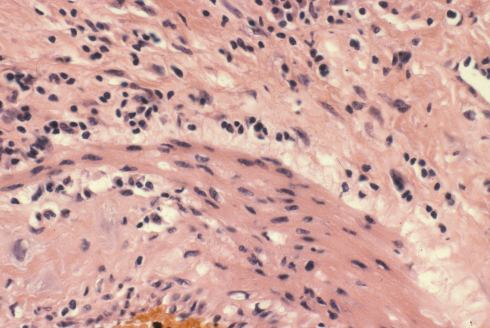

Un-remodeled muscular spiral arteries are usually found in the membranes. They may be difficult to distinguish from the deeper, smaller radial arteries. The most striking pathologic lesion of these spiral arteries is acute atherosis, which will be discussed below. The arteries may demonstrate numerous mononuclear cells in or around the wall of the spiral arteries, or even eosinophils (Figs 6a, 6b, 7).

Fig 6b: A higher power of one of the spiral arteries in the previous section demonstrates the lymphocytic appearance of the inflammation. H&E 40x